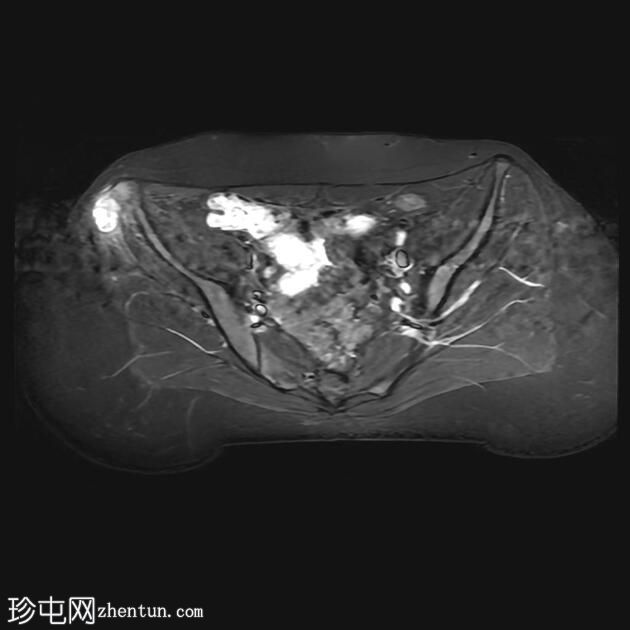

MRI

轴位T2加权像

脂肪抑制像

臀中肌髂骨起点处前侧全层撕裂,伴有充满液体的间隙,以及髂骨髓水肿。

MRI结果符合臀中肌近端髂骨起点处全层撕裂的

影像

学表现。